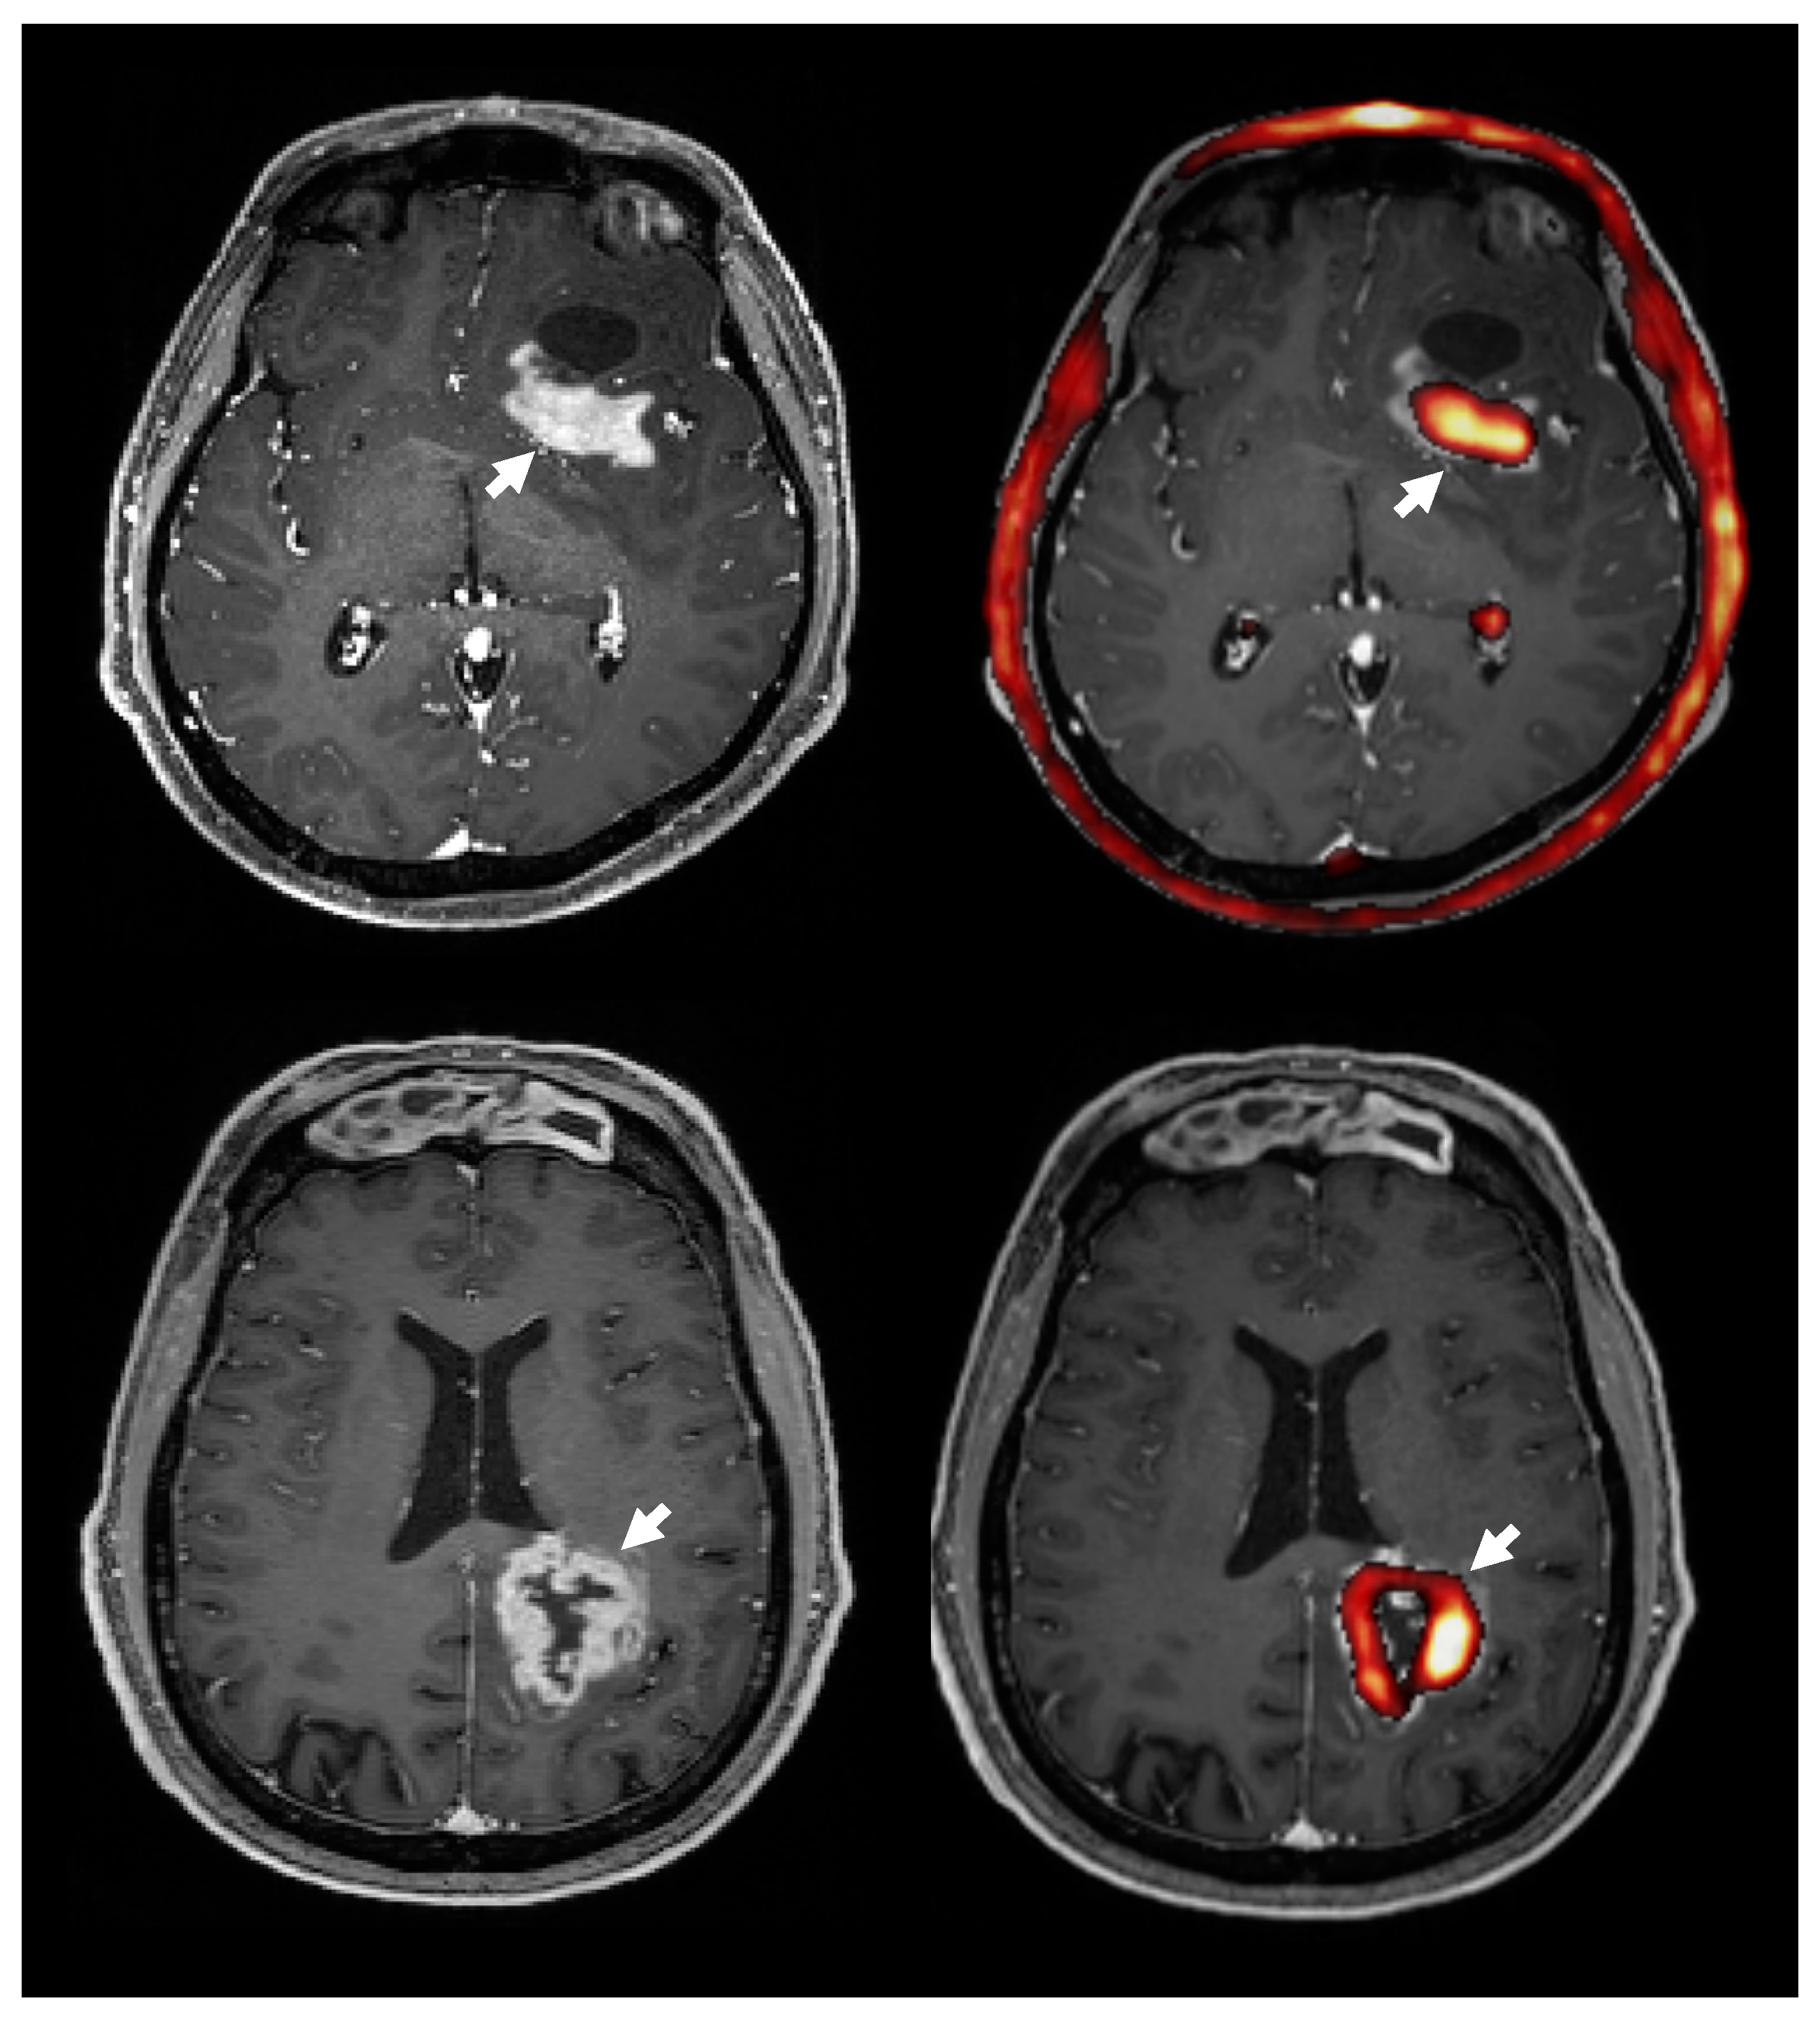

Seven of the patients showed regions of contrast enhancement (3 WHO grade IV, 2 WHO grade III, 1 WHO grade II, 1 WHO grade I). Overlaying areas of highest 18F-FMC uptake on contrast-enhanced T1 weighted imaging (Figure 5) showed that on average 94% of the volume of contrast enhancement had an uptake above the threshold, which was defined as three times the uptake in contralateral white matter. Of the 7 patients showing regions of contrast enhancement, 5 showed high 18F-FMC uptake in 100% of the contrast enhancing regions, 1 in 92% (WHO grade IV), and 1 in 67% (WHO grade III). In comparison, when analysing hyperintense regions on T2 FLAIR and excluding regions of contrast enhancement in these 7 patients, an average of 39% (min 1%, max 89%) of the volume of non contrast enhancing tumour showed 18F-FMC uptake greater than the threshold. Of note, the grade I DNET, which was excluded from formal comparative analysis, showed contrast enhancement and markedly elevated 18F-FMC uptake.

Figure 5.

The 18F-FMC uptake (right, red) and contrast enhancement on MRI (left) in two patients with GBM. Overlaying 18F-FMC PET onto post-contrast T1 weighted MRI showed that areas of contrast enhancement had a high 18F-FMC-uptake (white arrows). Overall, an average 94% of contrast enhancing regions had a 18F-FMC-uptake above the threshold, which was defined as three times that in the contralateral white matter. Note the normal high uptake in the choroid plexus and bone marrow.